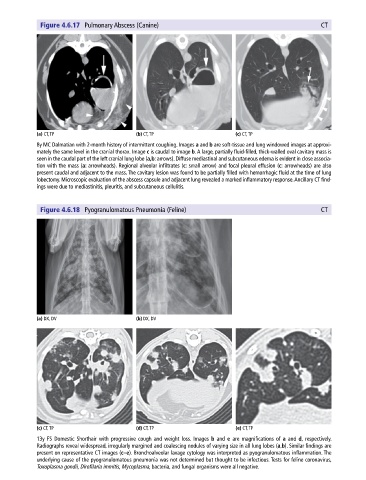

Figure 4.6.17 Pulmonary Abscess (Canine) CT

(a) CT, TP (b) CT, TP (c) CT, TP

8y MC Dalmatian with 2‐month history of intermittent coughing. Images a and b are soft‐tissue and lung windowed images at approxi-

mately the same level in the cranial thorax. Image c is caudal to image b. A large, partially fluid‐filled, thick‐walled oval cavitary mass is

seen in the caudal part of the left cranial lung lobe (a,b: arrows). Diffuse mediastinal and subcutaneous edema is evident in close associa-

tion with the mass (a: arrowheads). Regional alveolar infiltrates (c: small arrow) and focal pleural effusion (c: arrowheads) are also

present caudal and adjacent to the mass. The cavitary lesion was found to be partially filled with hemorrhagic fluid at the time of lung

lobectomy. Microscopic evaluation of the abscess capsule and adjacent lung revealed a marked inflammatory response. Ancillary CT find-

ings were due to mediastinitis, pleuritis, and subcutaneous cellulitis.

Figure 4.6.18 Pyogranulomatous Pneumonia (Feline) CT

(a) DX, DV (b) DX, DV

(c) CT, TP (d) CT, TP (e) CT, TP

13y FS Domestic Shorthair with progressive cough and weight loss. Images b and e are magnifications of a and d, respectively.

Radiographs reveal widespread, irregularly margined and coalescing nodules of varying size in all lung lobes (a,b). Similar findings are

present on representative CT images (c–e). Bronchoalveolar lavage cytology was interpreted as pyogranulomatous inflammation. The

underlying cause of the pyogranulomatous pneumonia was not determined but thought to be infectious. Tests for feline coronavirus,

Toxoplasma gondii, Dirofilaria immitis, Mycoplasma, bacteria, and fungal organisms were all negative.